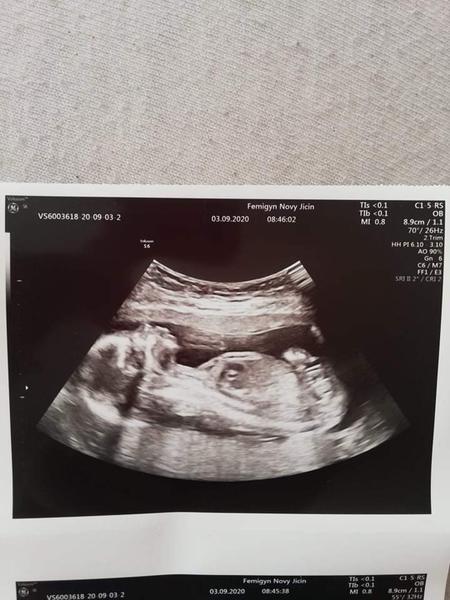

Ahoj maminky a budoucí maminky 😉 Prosím, poradila byste mi některá, co vidíte na fotce z ultrazvuku ve 20. týdnu za pohlaví? Určitě jste foteček viděly už mraky, proto vás žádám o radu...Nechci nikoho ovlivnit, proto svůj tip řeknu později 🙂 Děkuju moc!!!

@miiiissssanek cca 18. týden

Ze 17. tt dávala jiná nastávající maminka 😊